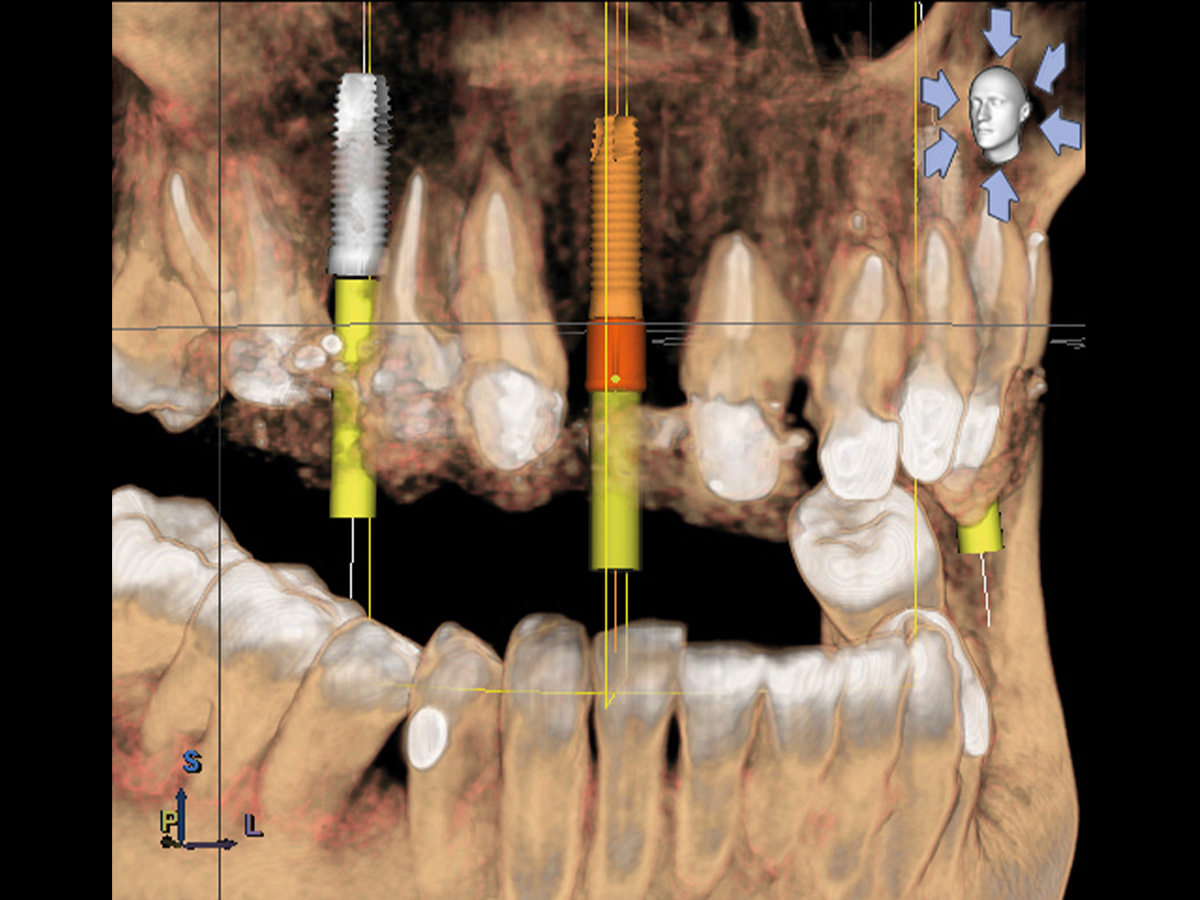

Abbildung 1

Präoperative Ausgangslage der atrophen Knochensituation mit geplantem Implantat.

Abbildung 2

DVT mit Implantatplanung zeigt die atrophe Knochensituation mit geplantem Implantat.

Abbildung 3

3D-Darstellung der geplanten Implantatposition.